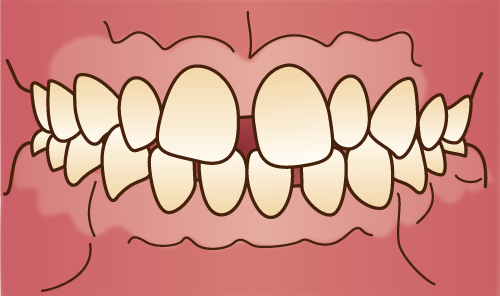

過蓋咬合(上顎前突)

上顎前突

○上顎の過成長、または、下顎が上顎に対して後方に移動している状態

過蓋咬合

○上顎前歯が下顎前歯に垂直的に深く咬み合っている状態。

○上顎前歯が下顎前歯の2/3以上被っている状態

○指しゃぶりや吸唇癖などの口腔習癖や、おしゃぶりの常用による。○口呼吸(鼻づまり)による。○遺伝的な場合がある。 |